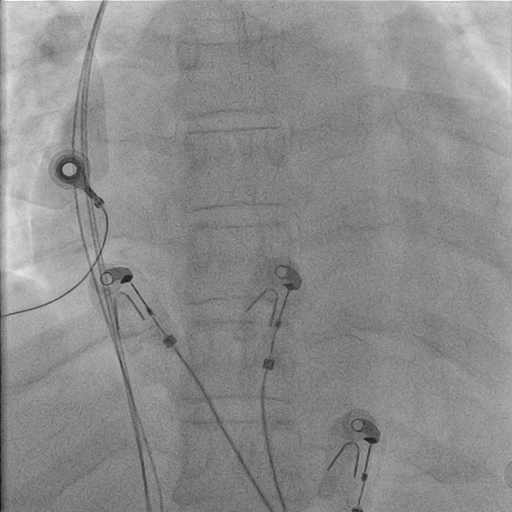

Puncture with venogram